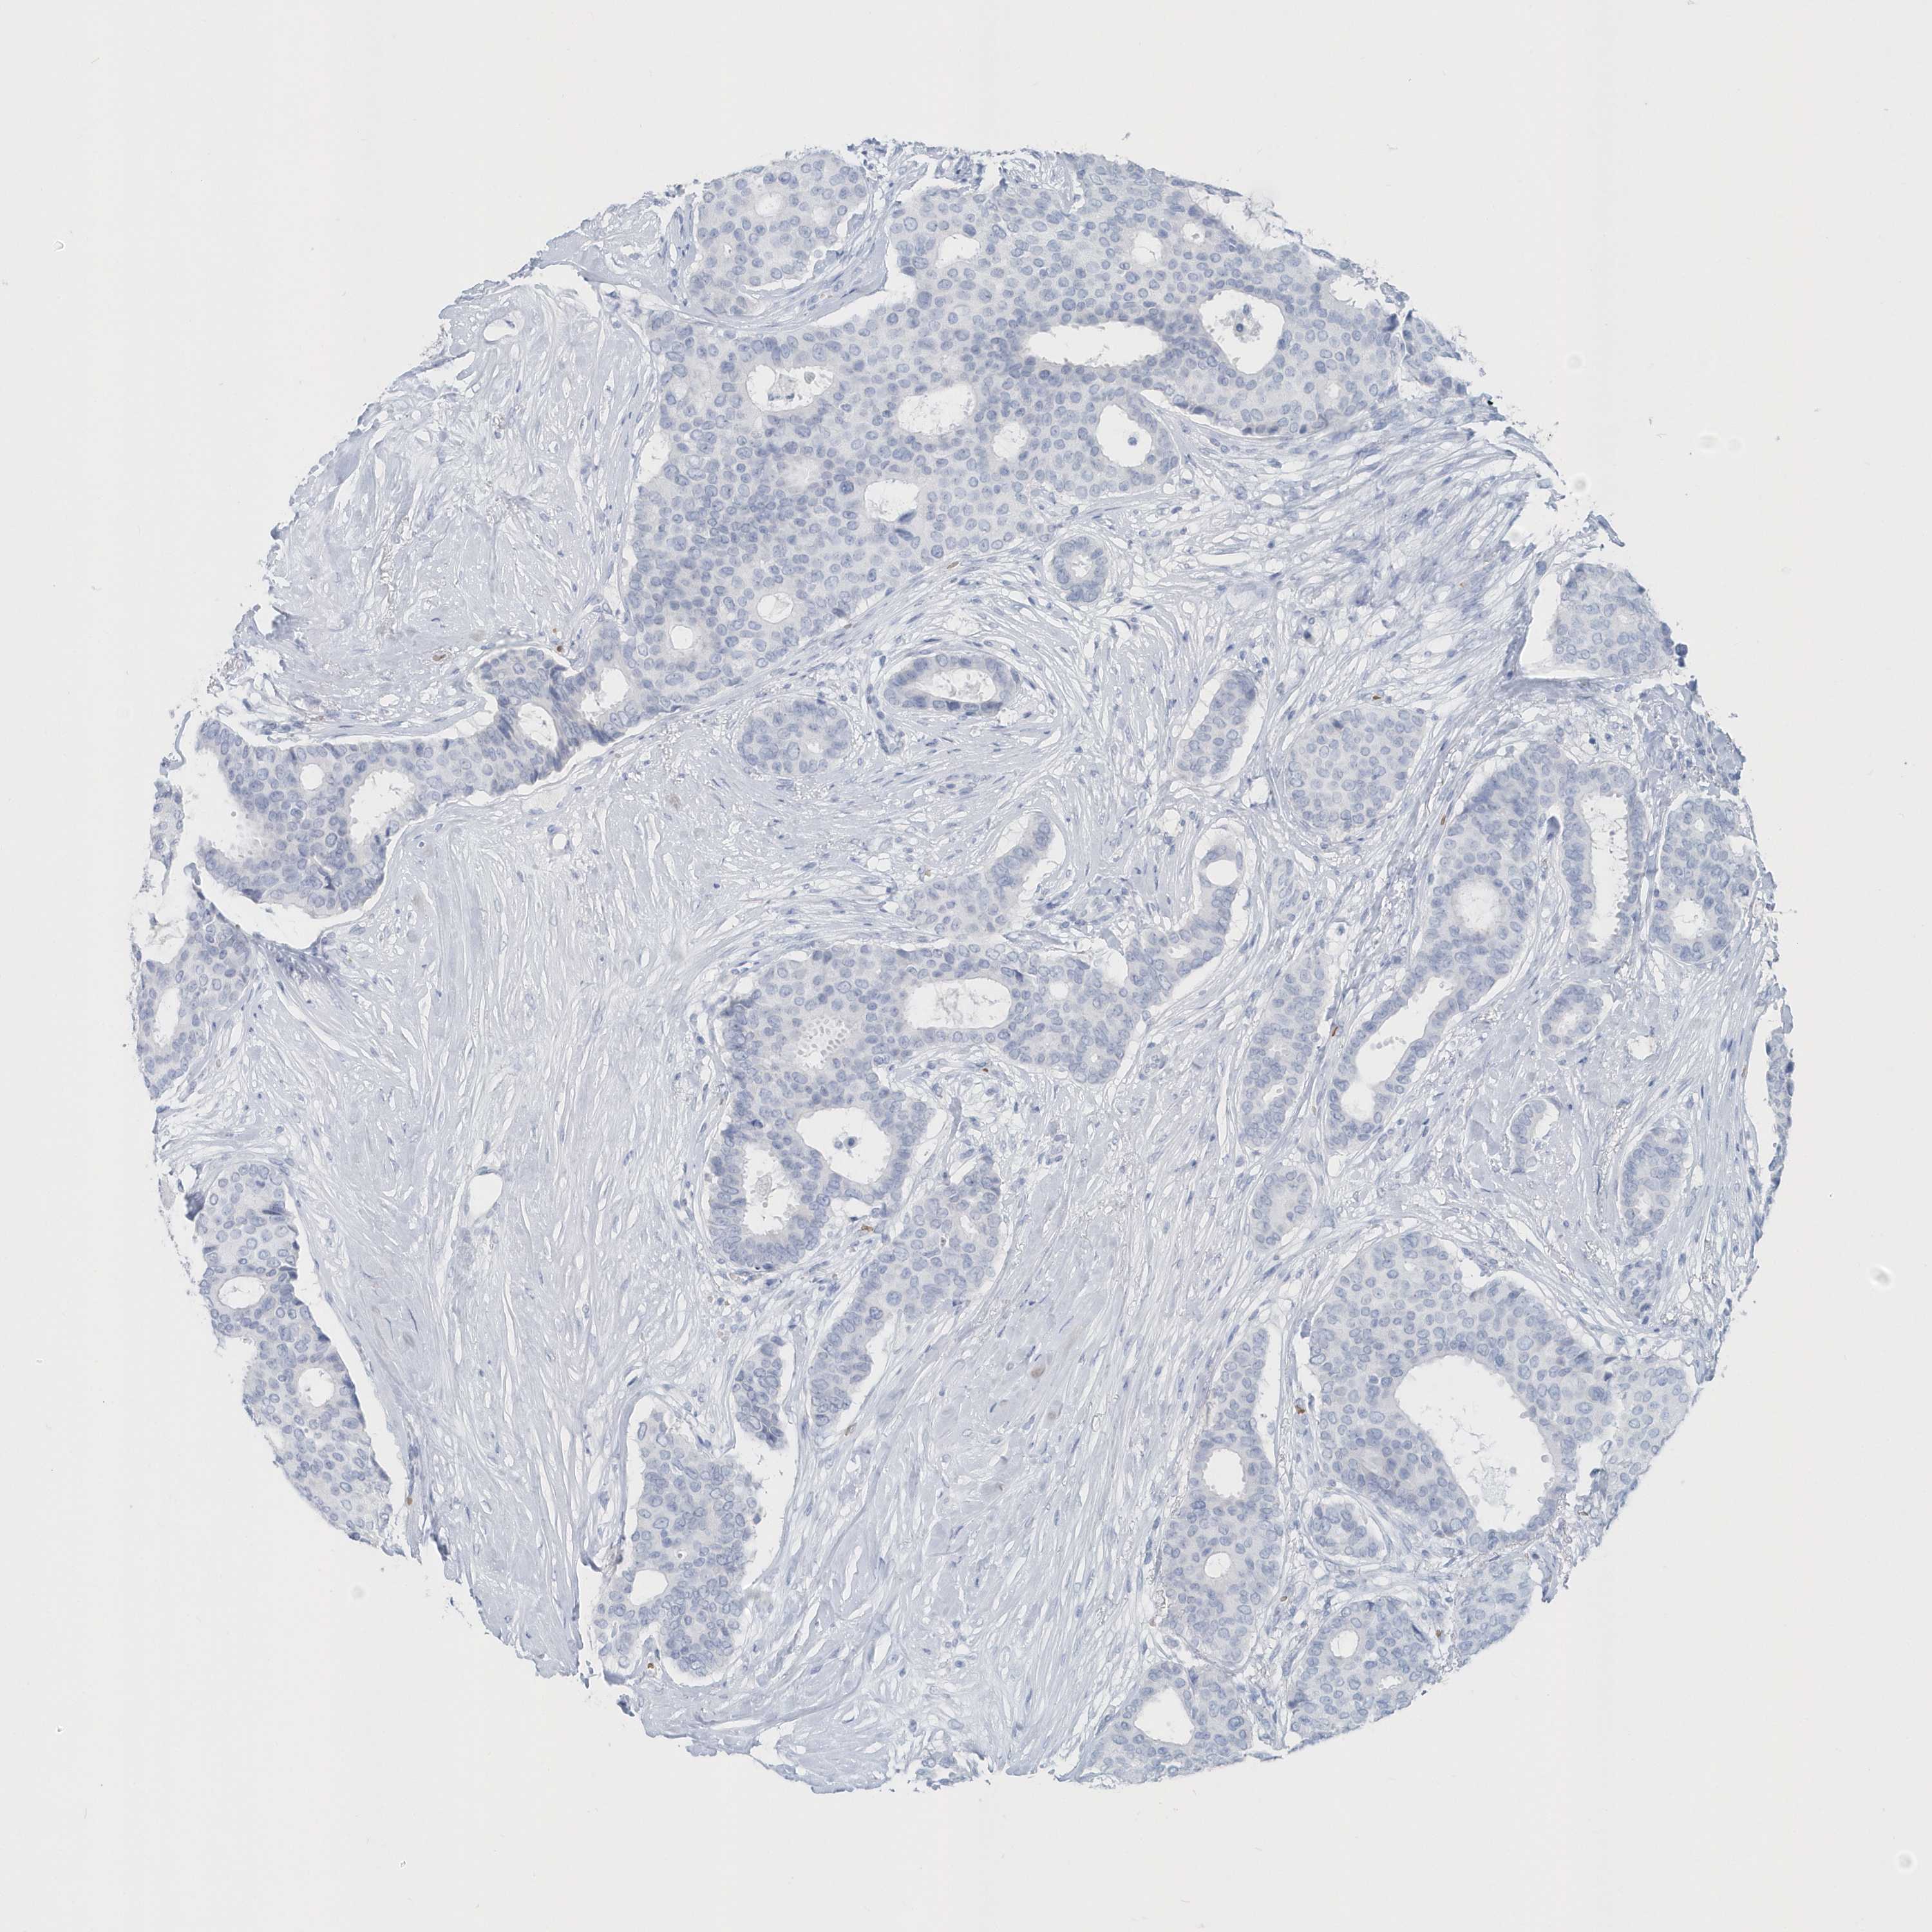

BRCA TCGA BRCA VALIDATION PROTEIN EXPRESSION

ANTIBODIES

AND

VALIDATION